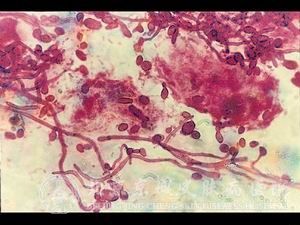

目前治疗念珠菌病的外用诊疗是什么?治疗念珠菌病除了可以利用内用诊疗进行治疗,还可以通过外用诊疗。由于很多念珠菌病患者不了解治疗念珠菌病的外用诊疗,导致疾病更加严重。现在北京京城皮肤医院的皮肤专家就为我们介绍治疗念珠菌病的外用诊疗是什么?

北京京城皮肤医院指出,外用诊疗治疗念珠菌病只对皮肤粘膜念珠菌,可以利用一些常用的外用药进行治疗,也可以做出膏药,乳剂,溶液进行使用。

4.念珠菌病是什么